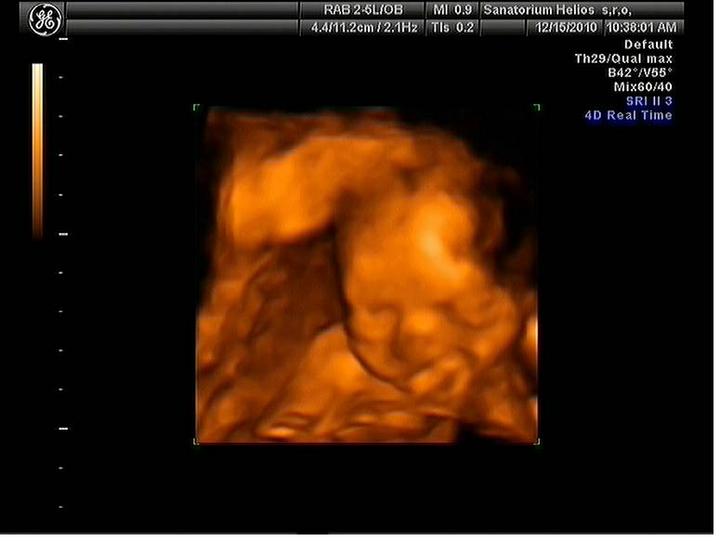

Jsme zpátky z dovolené, prcek v bříšku ani moc nezlobil🙂

Za 7 hodin uvidíme naši fazolku, nemůžu se dočkat a asi proto nemůžu spát. Strašně se těším. Snad bude vše v pořádku.